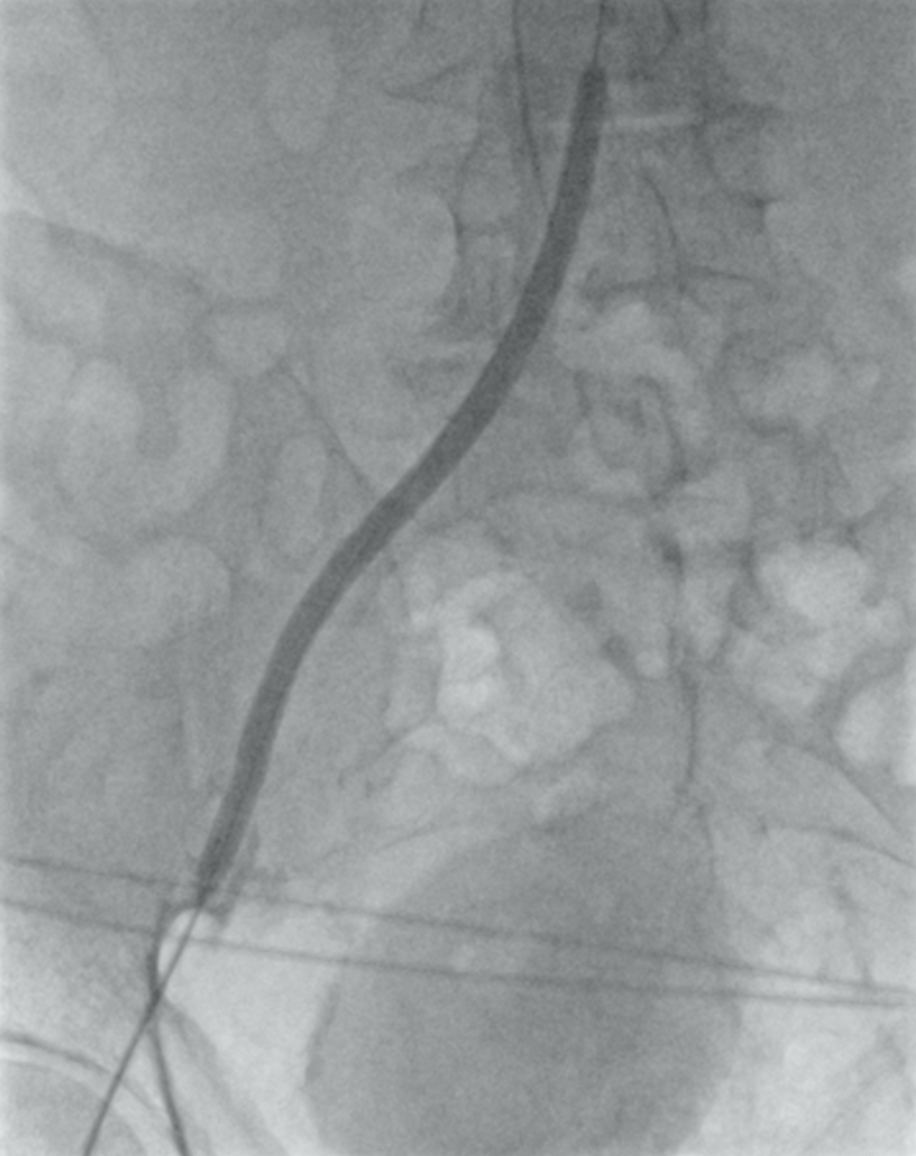

Хирург принял решение о выполнении эндоваскулярной реканализации окклюзированного сегмента наружной подвздошной артерии. При поддержке диагностического катетера выполнена ретроградная реканализация НПА, проводник проведен через окклюзию в инфраренальный отдел аорты. Выполнена предилатация поражения НПА справа баллонным катетером, был получен антеградный кровоток по наружной подздошной артерии (рис. 3).

Рисунок 3. Предилатация поражения НПА баллонным катетером.